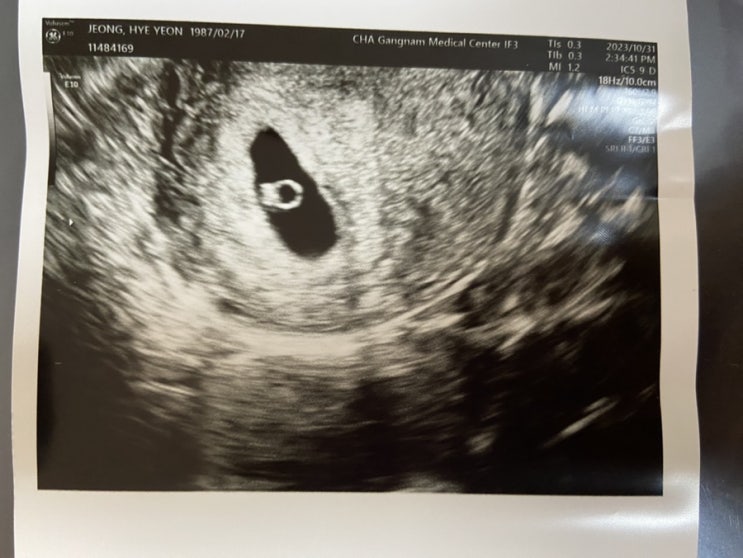

[난임휴직일기] 임신 6주 초음파 확인 #다이아반지?! #심장소리 #직장 보고

오늘 다녀왔습니다 강남차… 짜잔~ 왕 다이아 반지 초음파 확인하고 왔습니다 ㅎㅎ 심지어 심장 소리도 듣...